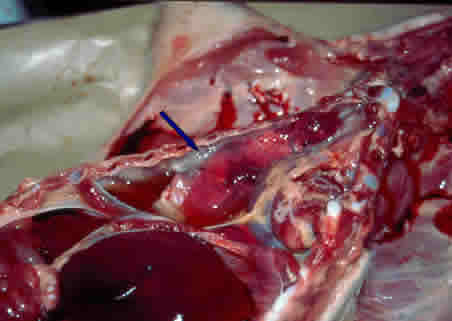

. Cavité thoracique : péricardite fibrineuse, pleurésie fibrineuse (pas d'œdème pulmonaire).

Epanchement

pleural

|

Péricardite

+ pleurésie

|

Poumons

avec dépôts de fibrine

|

|

Poumons

avec dépôts de fibrine

|